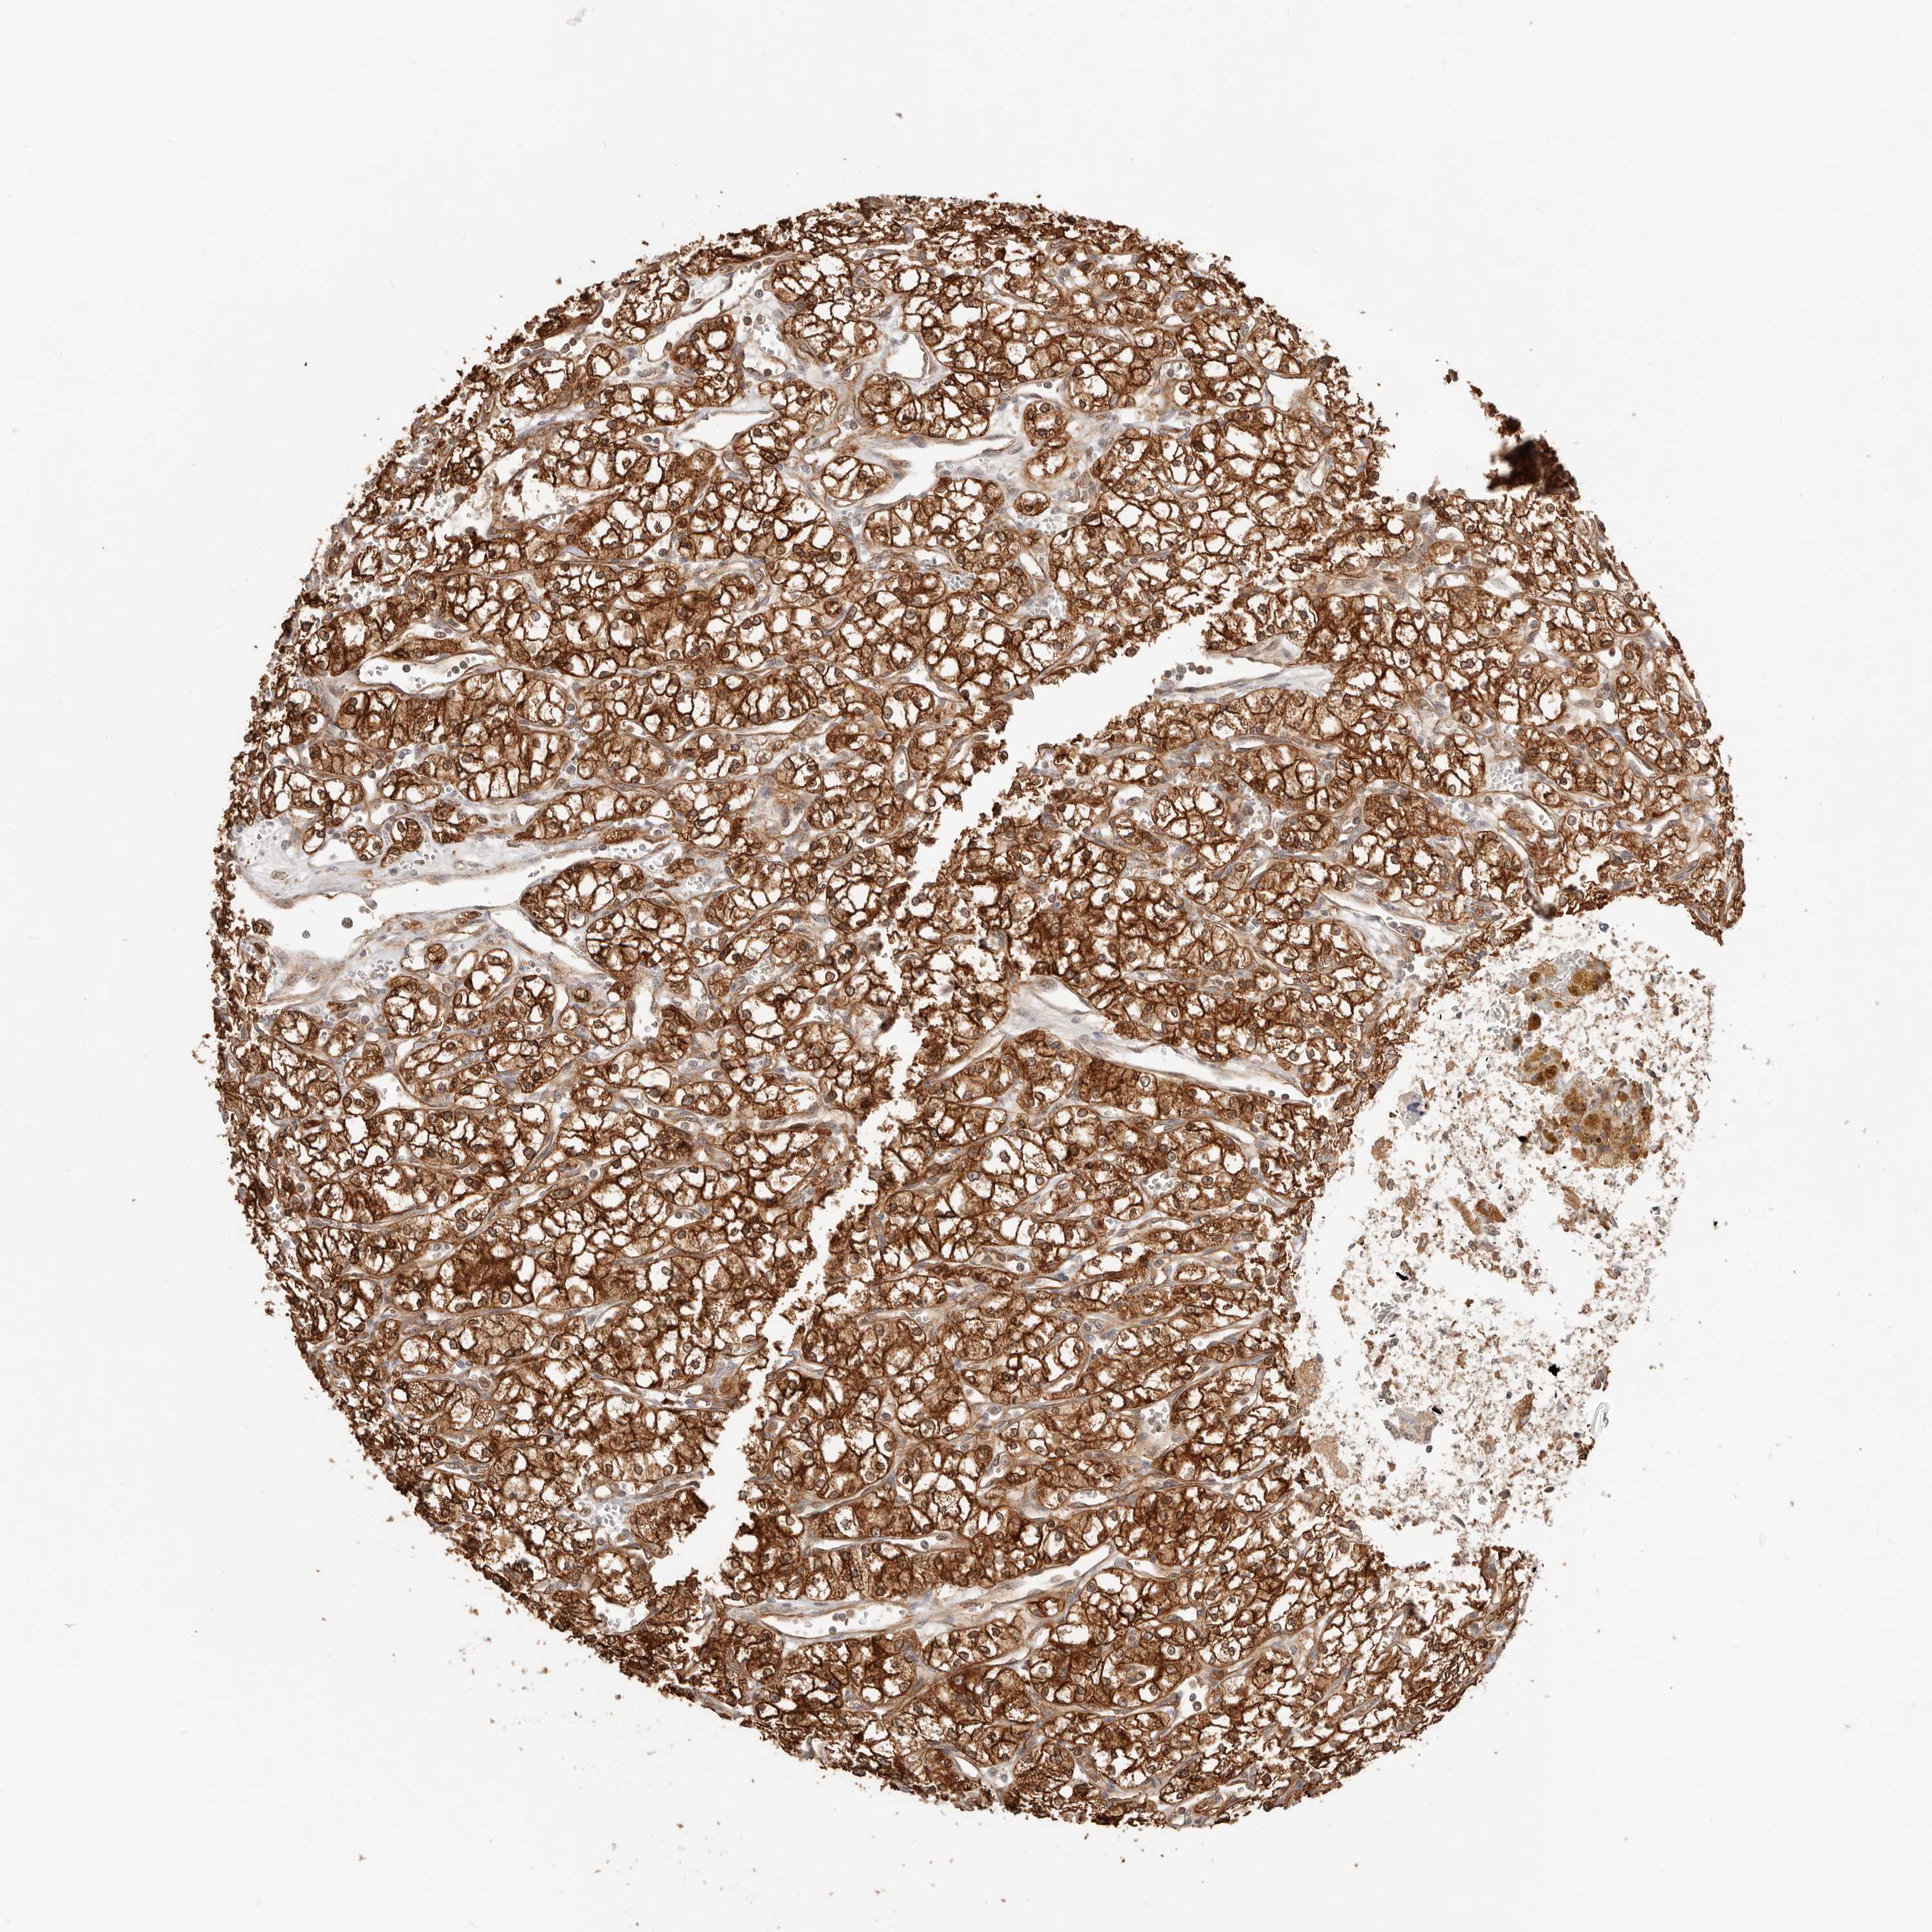

KIDNEY RENAL CLEAR CELL CARCINOMA (TCGA) - Interactive survival scatter ploti

The Survival Scatter plot shows the clinical status (i.e. dead or alive) for all individuals in the patient cohort, based on the same data that underlies the corresponding Kaplan-Meier plots. Patients that are alive at last time for follow-up are shown in blue and patients who have died during the study are shown in red.

The x-axis shows the expression levels (FPKM) of the investigated gene in the tumor tissue at the time of diagnosis. The y-axis shows the follow-up time after diagnosis (years). Both axes are complimented with kernel density curves demonstrating the data density over the axes. The top density plot shows the expression levels (FPKM) distribution among dead (red) and alive patients (blue). The right density plot shows the data density of the survived years of dead patients with high and low expression levels respectively, stratified using the cutoff indicated by the vertical dashed line through the Survival Scatter plot. This cutoff is automatically defined based on the FPKM cutoff that minimizes the p-score. The cutoff can be changed by dragging the vertical line or by entering a cutoff value in the square labeled "Current cut-off".

Under the Survival Scatter plot the p-score landscape (black curve; left axis) is shown together with dead median separation (red curve; right axis). Dead median separation is the difference in median mRNA expression between patients who have died with high and low expression, respectively. It is calculated as follows: median FPKM expression of dead patients with high expression - median FPKM expression of dead patients with low expression. This is intended to aid the user in visually exploring custom cutoffs and the associated p-scores and dead median separation.

Individual patient data is displayed and can be filtered by clicking on one or more of the category buttons on the top of the page. Categories describing expression level and patient information include: high, low, alive, dead, female, male and tumor stages. The scale of the x-axis can be toggled between linear and log-scale by clicking on the "x log" button. Mouse-over function shows TCGA ID, patient information and mRNA expression (FPKM) for each patient.

& Survival analysisi

Kaplan-Meier plots summarize results from analysis of correlation between mRNA expression level and patient survival. Patients were divided based on level of expression into one of the two groups "low" (under cut off) or "high" (over cut off). X-axis shows time for survival (years) and y-axis shows the probability of survival, where 1.0 corresponds to 100 percent.

HEXD is validated prognostic, high expression is favorable in Kidney Renal Clear Cell Carcinoma (TCGA)

: 6.02

Average pTPM 8.6

Number of samples 521